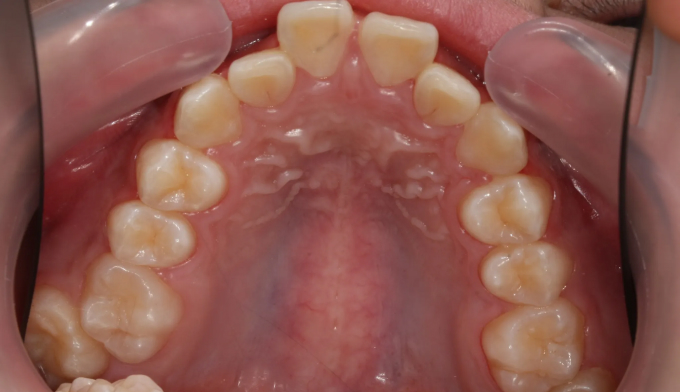

앞니가 돌출되어 있으면서 동시에 위 맨끝 어금니가 아래 어금니와 사선으로 물려있는 가위교합이 관찰됩니다.

가위교합은 음식물 섭취에 있어서도 비효율적이지만, 올바른 잇솔질을 하기가 어려워 구강위생에도 좋지 않아 교정이 필요합니다.